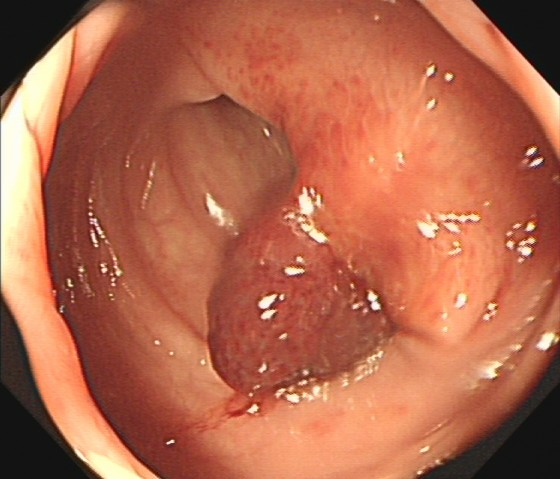

(1)赖女士(62岁,横结肠息肉,图1)

图1

病理诊断:管状腺瘤,伴低级别上皮内瘤变。

解读:管状腺瘤是最常见的腺瘤性息肉。低级别上皮内瘤变意味着腺体结构和细胞出现了轻度到中度的异常改变,是明确的癌前状态。此阶段积极切除并定期复查,可有效阻断癌变进程。距离癌:一步之遥,癌前病变中期。